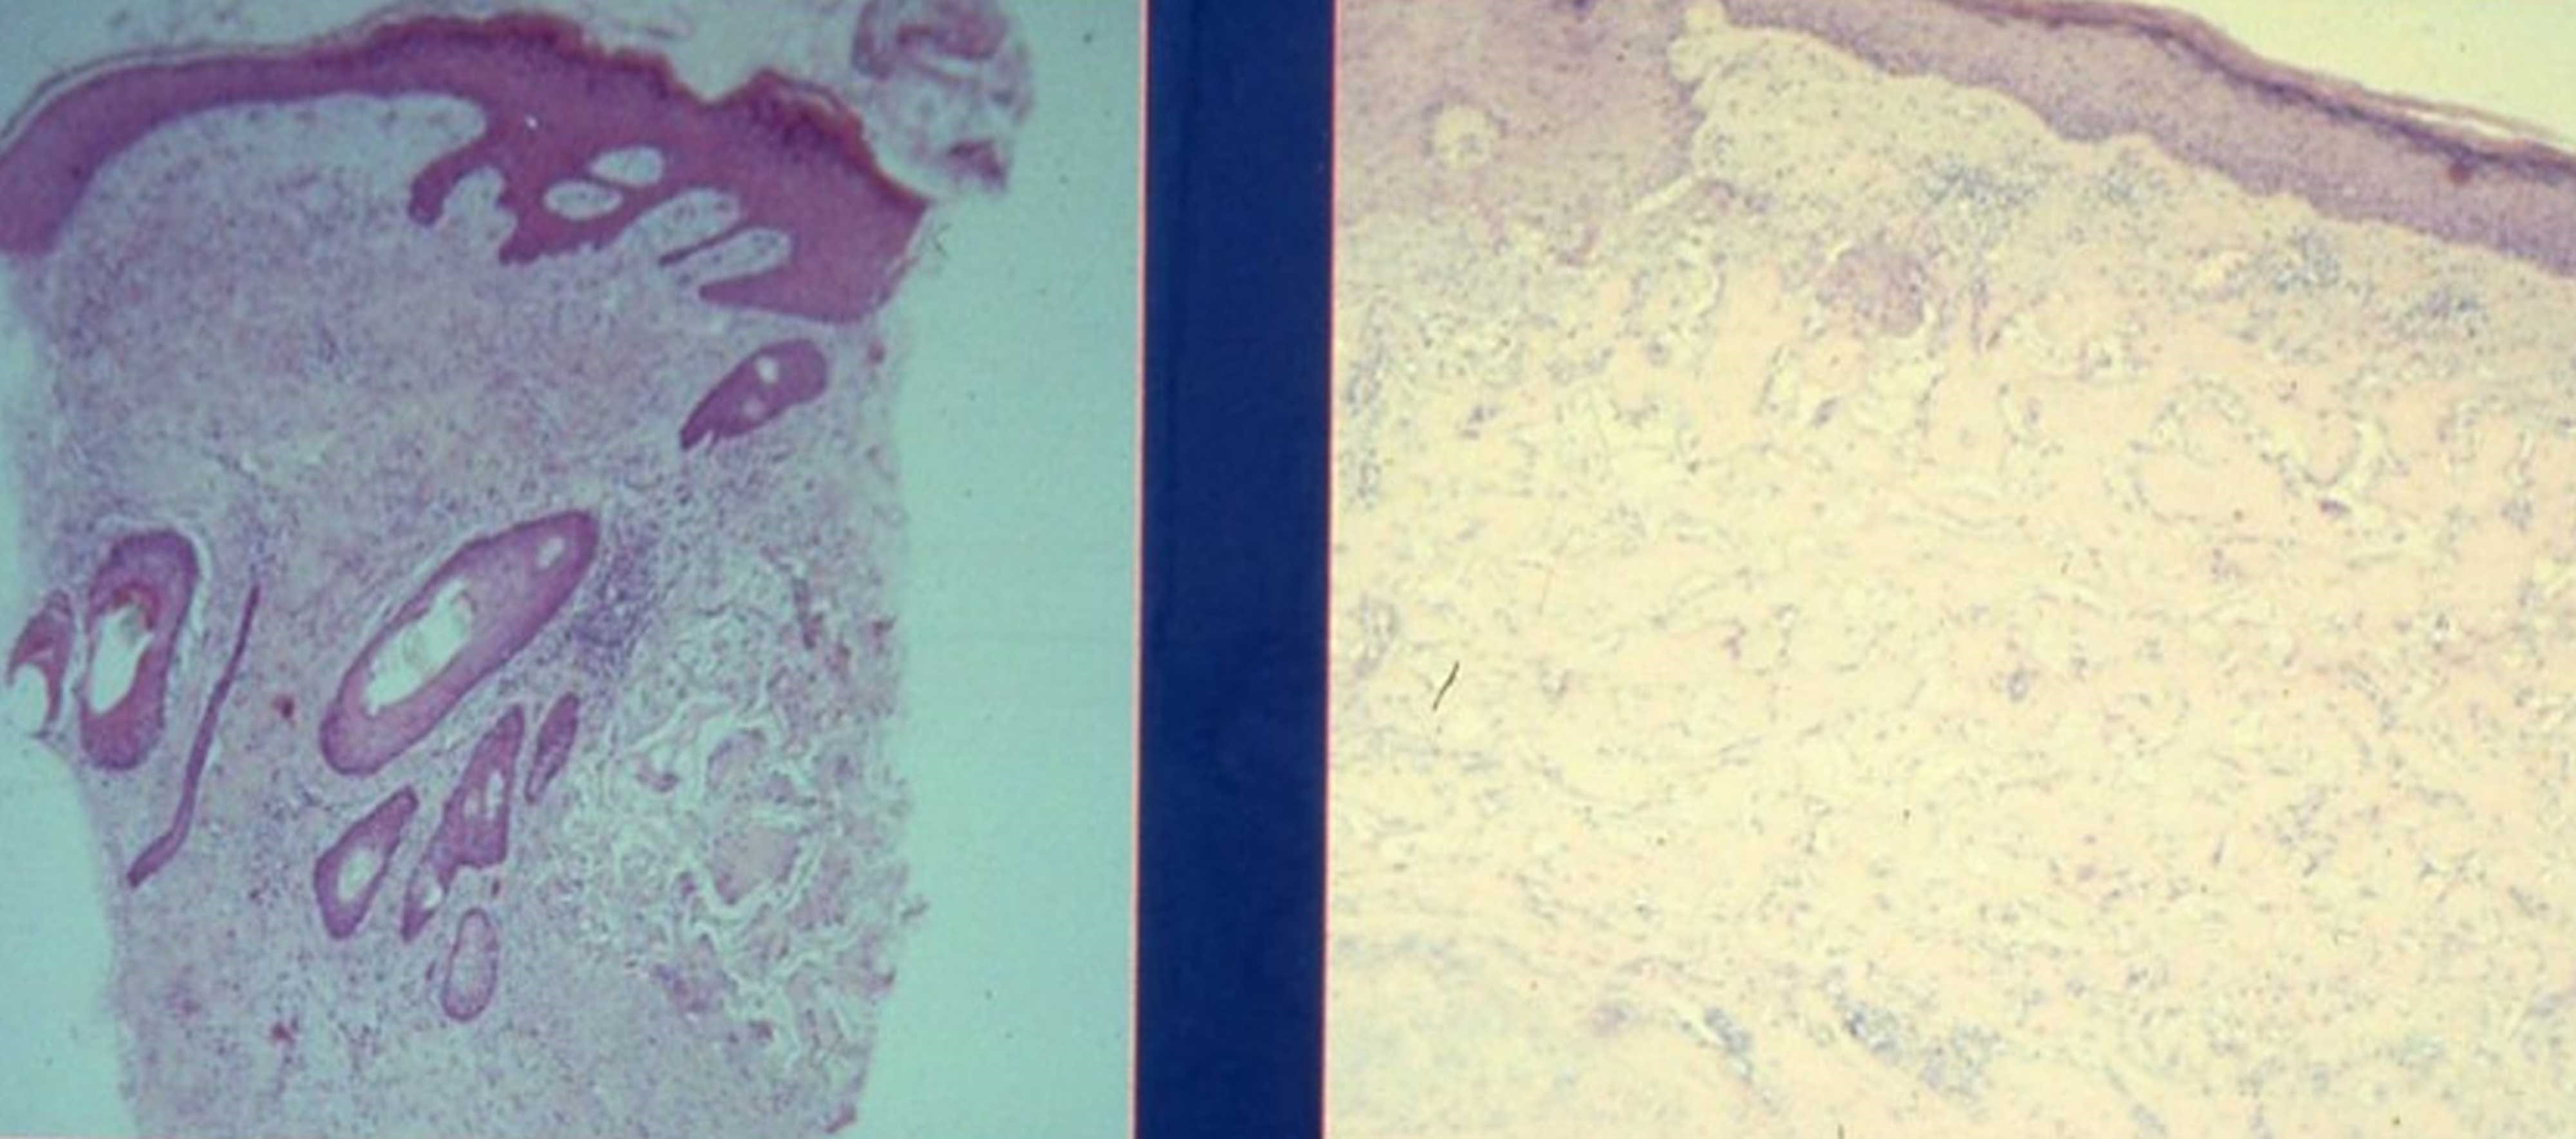

Figure 3a (left): Haematoxylin and eosin stain showing the survival of transplanted hair follicle with adjacent rete folds around the integrated hair follicle.

Figure 3b (right): Histology of the neo epidermis with flattish rete pegs and a revascularised neo-dermis full of collagen and fibroblasts.